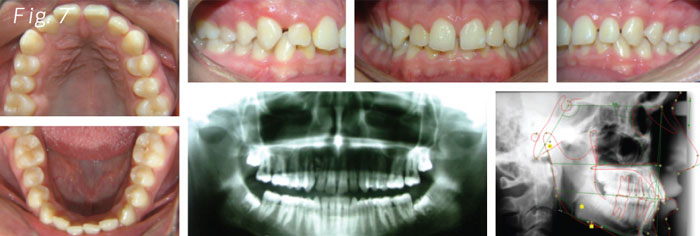

A 17-year-old patient (Fig. 6) wanted to close the spaces between the front teeth (Fig. 7). He didn't want the braces to show so he came to the office for lingual braces.

The patient presented a challenging combination of circumstances: dental spaces, lower crowding and overbite. The main problem we saw on the panoramic X-ray was the presence of an odontoma between the upper right lateral and cuspid.

It can be diagnosed in adolescence; it is asymptomatic, and usually found by X-rays. We observed disorganized dental tissue and it's well delimitated by a radiolucent area (Fig. 7).